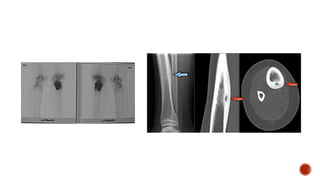

 Se caracteriza por formar un nido de 1 a 2 cm, muy vascularizado, osteolítico, que es la

parte activa del tumor, rodeado de una zona de neoformación ósea y esclerótica.

 Se presenta entre los 10 y los 35 años, predomina en hombres 2:1.

 Afecta principalmente los huesos largos, donde se ubica en 65% de los casos.

 Los sitios de localización más frecuentes son: tibia, cuello de fémur, diáfisis del fémur,

húmero, huesos del antebrazo, huesos de la mano y arco posterior de la columna.

 Tiene tres localizaciones: cortical, esponjosa y yuxtacortical.

 El cuadro clínico se caracteriza por dolor intenso, de predominio nocturno.

 Hipersensibilidad local.

 Para el diagnostico se debe solicitar la radiografía convencional, el cintigrama óseo,

la TC y la biopsia del tumor.

 Clínicamente esmucho más aparatoso que el osteoma.  Se caracteriza por formar un nido de 1 a 2 cm, muy vascularizado, osteolítico, que es la parte activa del tumor, rodeado de una zona de neoformación ósea y esclerótica.  Se presenta entre los 10 y los 35 años, predomina en hombres 2:1.  Afecta principalmente los huesos largos, donde se ubica en 65% de los casos.  Los sitios de localización más frecuentes son: tibia, cuello de fémur, diáfisis del fémur, húmero, huesos del antebrazo, huesos de la mano y arco posterior de la columna.

 Tiene treslocalizaciones: cortical, esponjosa y yuxtacortical.  El cuadro clínico se caracteriza por dolor intenso, de predominio nocturno.  Hipersensibilidad local.  Para el diagnostico se debe solicitar la radiografía convencional, el cintigrama óseo, la TC y la biopsia del tumor.